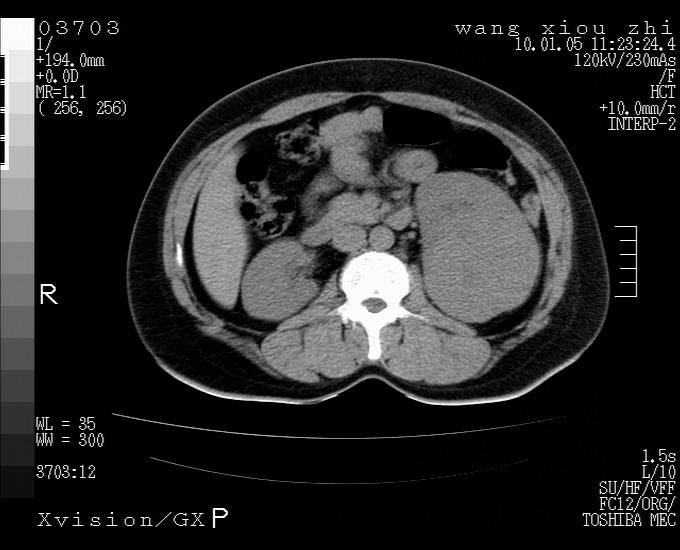

标题: CT23996:f,40.B超提示肿物。 [打印本页]

标题: CT23996:f,40.B超提示肿物。

左肾体积增大!下极见一密度略高团状软组织影!肾周结构组织未见明显异常!考虑左肾占位!建议增强!病史?

左肾占位性病变,建议增强。

实性影 肾癌

左肾占位性病变,考虑肾癌,建议增强 。

左肾占位,肾门及腹膜后淋巴结肿大,考虑透明细胞癌可能性大,建议增强